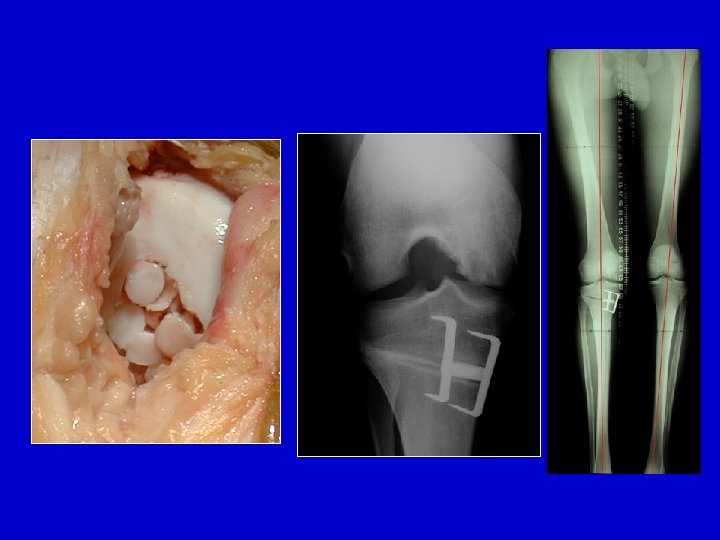

Trapianto osseo-cartilagineo a mosaico

Trapianto a mosaico

2 fori nella nicchia sono riempiti con 2 carote di tessuto osteo-cartilagineo

Prelievo dal bordo esterno della troclea

Osteocondrite del condilo femorale

Trapianto a mosaico : 6 mesi

Tentativo di trattamento con delle perforazioni di Pridie associate ad una osteotomia di scarico Adulto giovane

Nei soggetti con più di 65 anni : Protesi unicompartimentale o totale